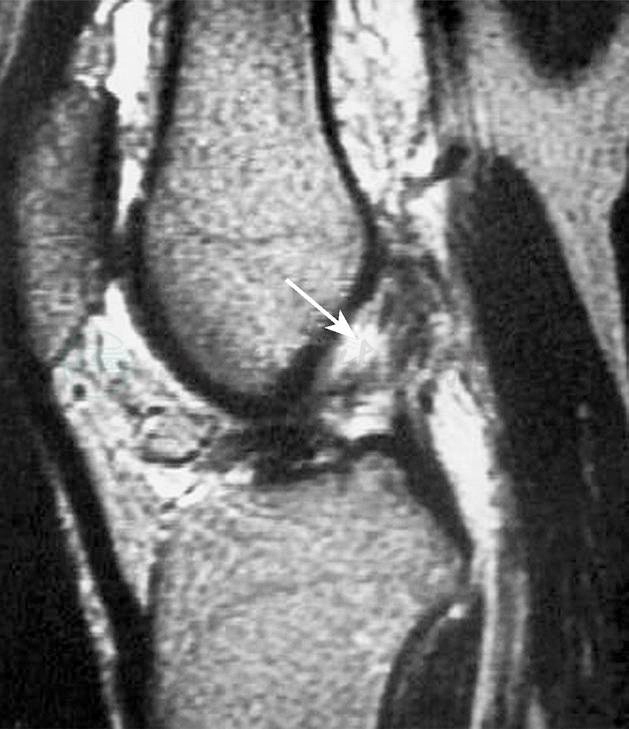

前交叉韧带急性损伤最初的磁共振成像表现为T2像的髁间窝血肿,以及韧带纤维的不连续(图9)。另外,在股骨外髁和胫骨平台后方会出现骨挫伤(图10),这种影像在前交叉韧带损伤中有很高的特异性。

图10前交叉韧带损伤后出现的骨挫伤

引自:实用骨科学(第2版).第2版.ISBN:978-7-117-22817-6.主编: